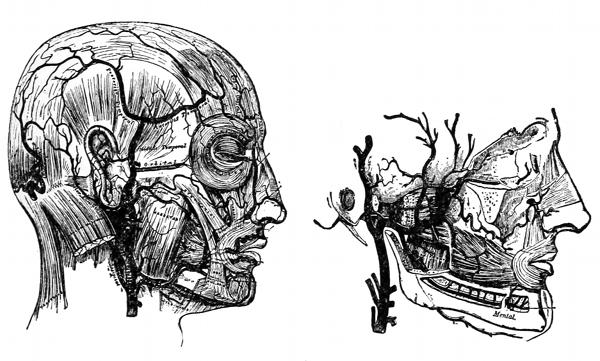

Fig. 3—Lymphatics of the head and neck.

B, the thoracic duct.

Fig. 4—Lymphatics of

the leg.